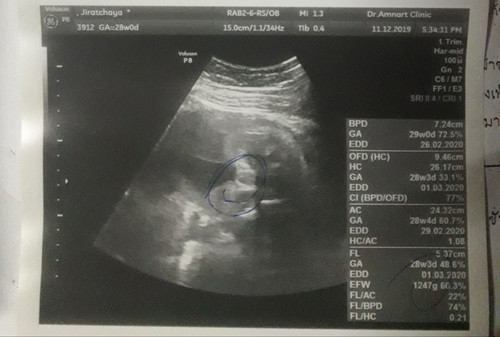

แบบนี้ผู้หญิงหรือผู้ชายค้ะ หมอว่าน่าจะผู้หญิงค้ะ28w